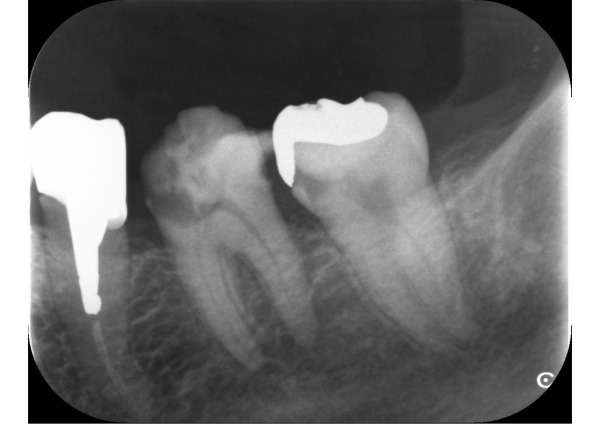

エックス線を撮影すると、右上奥歯2本、左下奥歯2本、左上前歯2本に虫歯が認められました。エックス線写真で診断するより実際は虫歯が深いことがあります。左下6番、左下7番、左上2番の計3本が神経に到達するほどの大きい虫歯でした。

1日目〜5日目 エックス線検査、歯周ポケット検査後、左下の根管治療を始めました。根管充填を完了するまで5回を要しました。